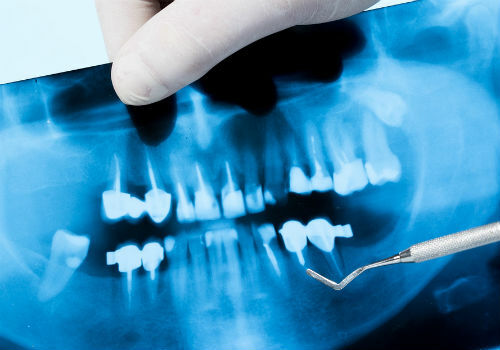

Анализ состояния зубов

Рентген-снимок зубов